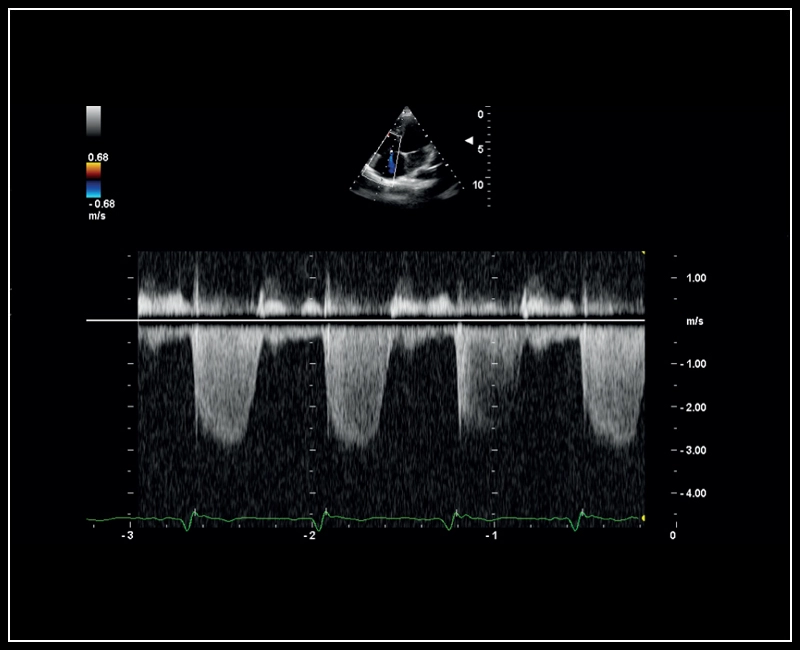

MyLab™Sigma - CW Doppler of Tricuspid regurgitation

MyLab™Sigma - CW Doppler of Tricuspid regurgitation